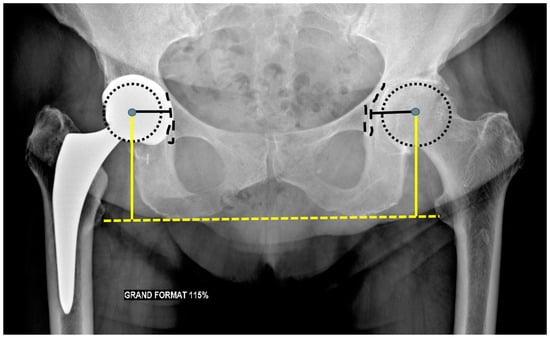

| Measurement | Normal Value | Consequences of Mispositioning |

|---|---|---|

| Leg Length | < 0.5–1 cm of differences between both sides | Increased discrepancy: gluteal and iliopsoas muscles affection |

| Acetabular side | ||

| Frontal acetabular inclination | 40 ± 15° | - Decreased: hip abduction limitation |

| - Increased: dislocation risk | ||

| Sagittal acetabular inclination | 35–40 ± 10° in standing position | - Increased: posterior impingement, anterior dislocation |

| 52 ± 11° in sitting position | - Decreased: anterior impingement between the cup and the neck, posterior dislocation | |

| Acetabular anteversion | 5–25° | - Lack of anteversion or retroversion: posterior dislocation, iliopsoas impingement |

| - Excessive anteversion: anterior dislocation | ||

| Acetabular center of rotation position | Similar to the contralateral hip | Lateralized: dislocation risk |

| Femoral Offset | 41–44 mm (or similar to contralateral hip) | - Decreased: limping, mobility limitation, and dislocation by gluteal muscles weakness |

| - Increased: gluteal muscles pain and polyethylene wear | ||

| Femoral side | ||

| Femoral Stem position | Neutral or slight valgus | Periprosthetic fracture and stress reaction in case of varus |

| Femoral Neck Anteversion | 10–15° | - Increased: anterior dislocation and ischio-femoral impingement |

| - Decreased: posterior dislocation | ||

| Femoral Head | Centered or slightly inferiorly located | - Particle disease if located upwards (wear) |